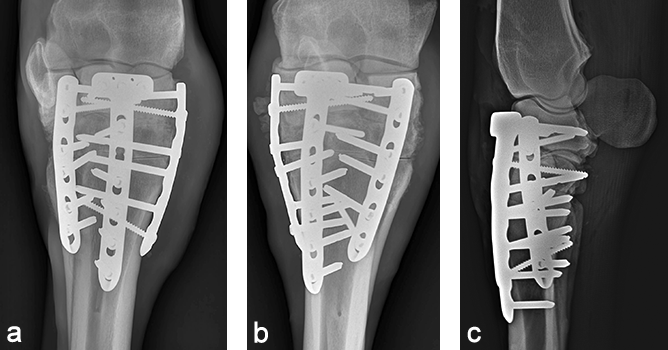

The day after admission, the mare was placed under general anesthesia in dorsal recumbency for a partial carpal arthrodesis of the right carpometacarpal and middle carpal joints. The middle carpal joint was examined arthroscopically, and all visible articular cartilage was removed by using a combination of manual (bone curette) and motorized (shaver/burr) instrumentation (Fig 6). A 4.5 mm drill bit was used to drill across the carpometacarpal joint surfaces. A cancellous bone graft harvested from the sternum was loosely packed into the repair through an arthroscopic portal with the leg in flexion. Following graft insertion, implants were placed using a minimally invasive technique, tunneling the plate under the skin and joint capsule, and stab incisions for screw insertions. A 6-hole LCP Equine T-plate 4.5 was applied to the dorsal aspect of the limb deep to the extensor tendons and joint capsule through an enlarged arthroscopic portal between the extensor carpi radialis and common digital extensor tendon using a plate passer. A 4.5 mm cortex screw was placed in the first hole of the shaft of the plate to compress the plate to the bone. Two 5.0 mm locking screws were placed in the holes of the horizontal portion of the plate to engage the intermediate carpal bone. A third 5.0 mm locking screw was placed into the radial carpal bone using the last hole of the horizontal portion of the plate (Fig 7). All remaining holes were filled with 5.0 mm locking screws except the second hole, which was left empty because the hole was directly over the carpometacarpal joint. A 6-hole narrow LCP 4.5 was applied dorsolaterally and a 6-hole narrow LCP 4.5 was placed dorsomedially in a similar manner. The skin incisions were closed in routine fashion, and a sterile dressing and full limb cast were applied. The mare recovered uneventfully from anesthesia with head and tail assistance.

The cast was removed 24 hours postoperatively, and a Robert- Jones bandage with caudal and lateral splints was maintained for 1 month. The mare made excellent postoperative progress with immediate full weightbearing on the operated leg. At 5 months postoperatively, radiographic evaluation confirmed excellent healing of the fracture and almost complete fusion of the middle carpal and carpometacarpal joints with preservation of the radiocarpal joint (Fig 8). At one year postoperatively, the mare showed a very good cosmetic aspect of the carpus, as well as an excellent locomotion at three gates, with only minor mechanical lameness due to reduction of carpal flexion (Fig 9).